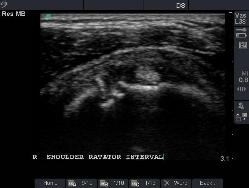

Proximal Subscapularis view, level of Coracroid Process

Normal image of Rotator Cuff Interval.